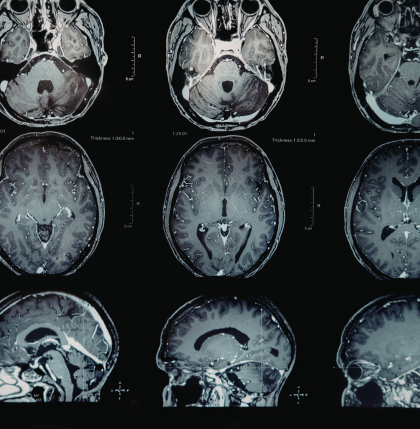

Focused ultrasound—often called MR-guided focused ultrasound (MRgFUS)—is a non-invasive procedure that uses highly targeted sound waves to treat specific areas of the brain involved in movement control.

During the procedure:

• Patients lie inside an MRI scanner

• Doctors use imaging to precisely guide ultrasound waves

• The waves create a small lesion in the brain area causing tremors

This disruption can reduce or even eliminate tremors, particularly on one side of the body.